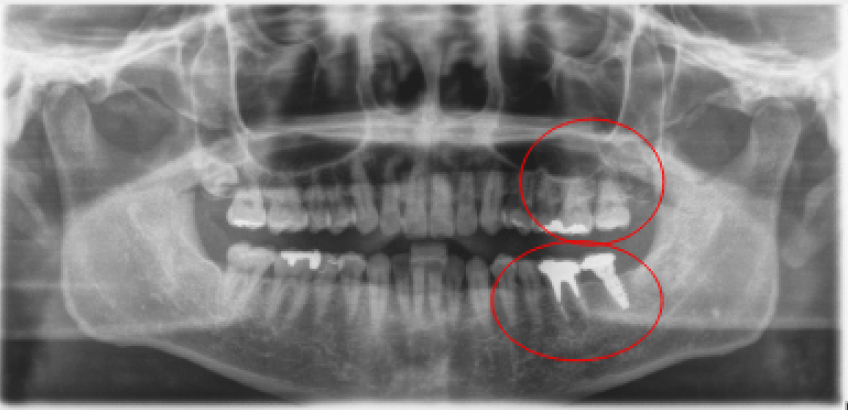

治療前治療後

| 治療内容 | インプラント奥歯1本・根管治療・矯正治療(圧下) |

|---|---|

| 患者様の年齢 | 40歳 |

| 患者様の性別 | 男性 |

| 治療期間 | 1年 |

| 治療回数 | 矯正治療合わせて50回程度 |

| 治療費用 | 根管治療1歯6万円/インプラント治療1歯50万円 矯正治療:1歯 10万円 |

| 治療で得られるメリット |

|

| 治療する際に起こる リスク・副作用 |